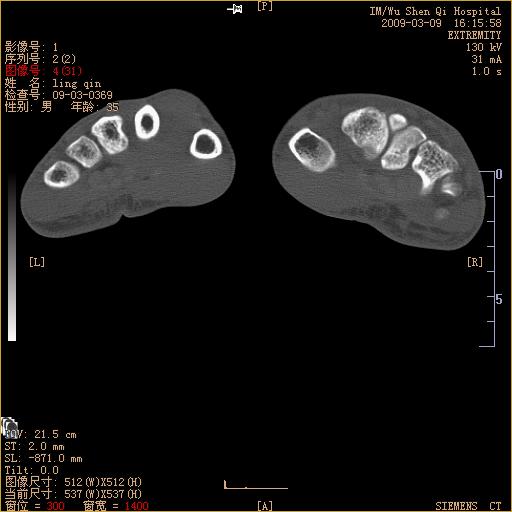

标题: CT18570:右手外伤10余天 [打印本页]

标题: CT18570:右手外伤10余天

请上传x线平片。舟状骨骨折可能大。

腕部有骨折、脱位,骨科面对ct片如何采取措施?三维一下。

请上传x线平片,腕骨多骨骨折

舟状骨骨折。

左侧舟骨及桡骨茎突骨折,第一掌骨基底部好像也有骨折,建议上传平片